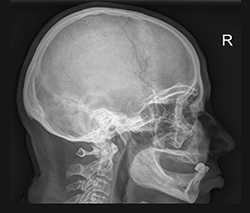

На обзорных рентгенограммах в прямой и боковой проекциях четко обрисовываются мозговой и лицевой череп. Толщина костей свода варьирует от 0,4 до 1 см. В области височной впадины она наименьшая, что на боковой рентгенограмме проявляется как просветление. В то же время в области теменных и затылочных бугров кости толще. На фоне мелкоячеистой структуры костей свода заметны различные просветления. К ним относятся древовидно разветвляющиеся борозды оболочечных артерий, широкие каналы и звездчатые разветвления диплоических вен, небольшие округлые или полулунные просветления пахионовых ямок и неотчетливые очертания пальцевых вдавлений (преимущественно в лобном отделе черепа). Естественно, на снимках демонстративно выступают содержащие воздух пазухи (лобные, решетчатые, околоносовые, пазухи основной кости) и пневматизированные ячейки височных костей.

Основание черепа хорошо видно на боковых и аксиальных снимках. На его внутренней поверхности определяются три черепные ямки: передняя, средняя и задняя. Границей между передней и средней ямками служат задние края малых крыльев основной кости, а между средней и задней - верхние края пирамид височных костей и спинка турецкого седла. Турецкое седло является костным вместилищем гипофиза. Оно рельефно вырисовывается на боковом снимке черепа, а также на прицельных снимках и томограммах. По снимкам оценивают форму седла, состояние его передней стенки, дна и спинки, его сагиттальный и вертикальный размеры.